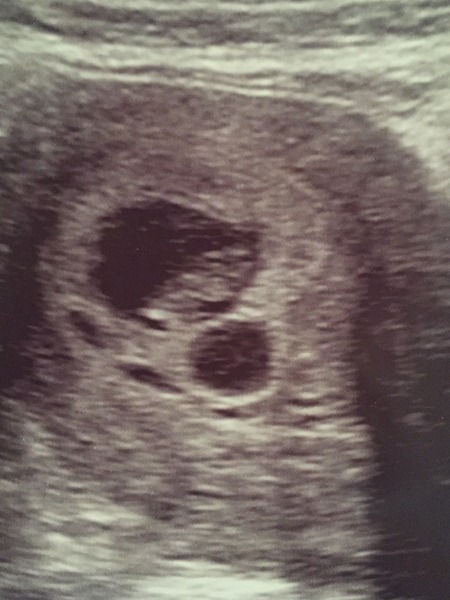

All ok on the scan today - measuring 8 weeks :)

I'm back there for a consultant scan tomorrow as there were what appeared to be cysts on the scan, and they now don't think that it was a second sac on last weeks scan. Will let you know how I get on tomorrow.

Fab northern! Can see tiny little baby on the picture too Smile. Wonder where the cysts are from then? Maybe ovarian, although you can get cervical cysts too (having had both myself!)

northern so pleased your scan went well. And relieved for you that you didn’t lose a twin in the end. I hope they get to the bottom of the cyst. I had a haematoma (clot) detected on my 6 week scan – it caused some spotting but had disappeared by my 8 week scan.

Yay northern that's great. Hope you go on ok tomorrow too. I had something called a luteal cyst spotted on my first early scan but exactly a wk later it had gone, hopefully it can be as simple as that for you too.